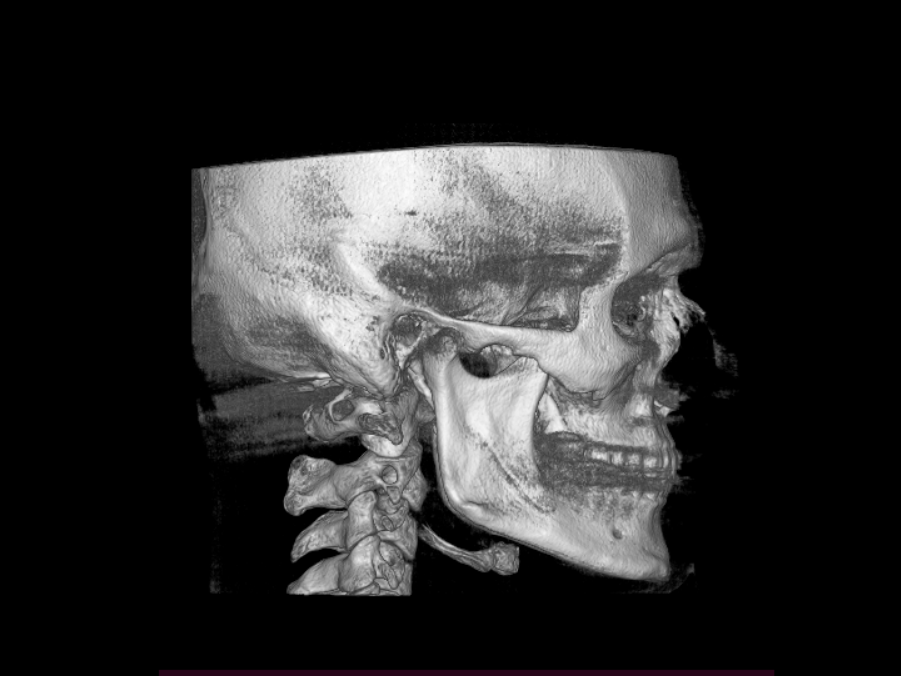

I’m wondering whether a genioplasty would be sufficient for me. My teeth are perfectly aligned, I have no breathing problems, and my only concern is a weak chin. I would like to achieve more width, projection, and some vertical height.